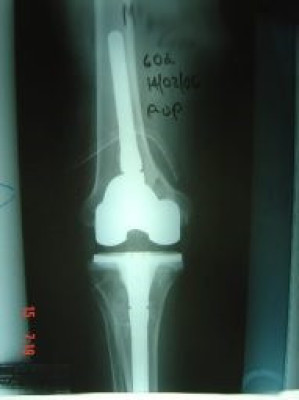

Revisión de prótesis de rodilla

Envíado por Dr. Ricardo Antonio Gómez G.